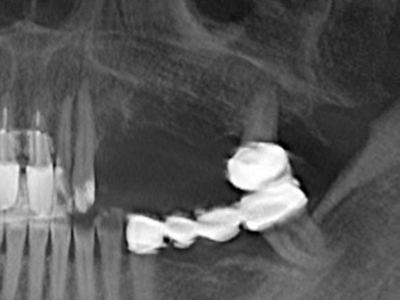

Препарацията на латерално ламбо по време на външен синус лифт е предизвикателство, особено за имплантолози с малък опит в хирургията. Отделянето на костното покритие на синуса без да бъде наранена лежащата отдолу Шнайдерова мембрана е само част от операцията – след установяване на подходящ достъп, линията на мембраната на синуса трябва внимателно да бъде повдигната, за да се направи място за материалите за аугментация или имплантите. Пиезохирургията е полезна за тази индикация по два начина: могат да се използват накрайници с диамантено покритие за избирателна костна аблация и едновременно с това, лежащата отдолу мукозна мембрана остава непокътната, когато процедурата е извършена прецизно. Ултразвуковите честоти също допринасят за отделяне на мукозната мембрана без усложнения – честотите се предават в пространството между мукозната мембрана и синуса чрез специални накрайници със заоблени ръбове (Cassetta, Ricci et al. 2012, Pereira, Gealh et al. 2014) (Rickert, Vissink et al. 2013). В резултат на това, не е изненадващо, че текущите доклади за външен синус лифт оценят положително пиезоелектрическите апарати, както и употребата на импланти с набраздени повърхности и костозаместителни материали. (Wallace, Tarnow et al. 2012).